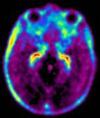

FDG

近年来,利用正电子发射断层扫描(PET)技术诊断肿瘤及癌症得到广泛的关注和应用。含氟化合物以及19F NMR是PET诊断技术发展的核心,这是因为正电子发射同位素18F的半衰期相对较长(t1/2=110min)。[18F]-2-氟-脱氧葡萄糖(FDG)是应用最为广泛的癌症诊断PET探针。研究表明,使用FDG进行PET显影在检测多种类型的肿瘤细胞方面比CT或MRI显影技术更有效。